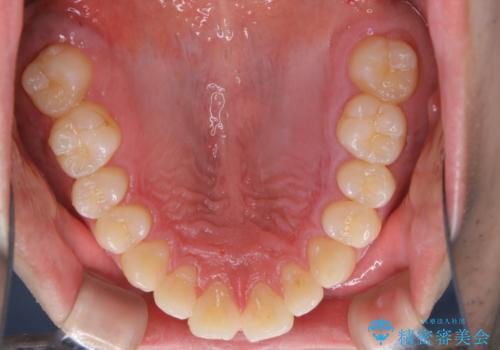

親知らずを抜いて1週間後にPMTC 歯のクリーニング

- 親知らずの抜歯後の約1週間後に抜糸(縫った部分の糸とり)で来院されました。その際、抜歯後は傷口が怖くて歯磨きが上手くできず、汚れや口臭が気になるためクリーニングも希望されました。

抜歯後は多少出血したり、違和感や痛みを感じたりすることがあります。そのため親知らずを抜いたり、外科的な処置をするといつも通りの歯磨きがしづらくなります。また、傷口の周りが心配で、歯ブラシをするのが怖くなるものです。抜歯後落ち着いたら、歯科医院にて専門の機械を使用しクリーニングをすることがおすすめです。抜歯前や後にPMTCを行うことで、お口の中の健康維持につながり、その後の感染・腫れ・口臭予防などになります。

親知らず抜歯後正常に治癒が進んでいれば1週間後から可能です。